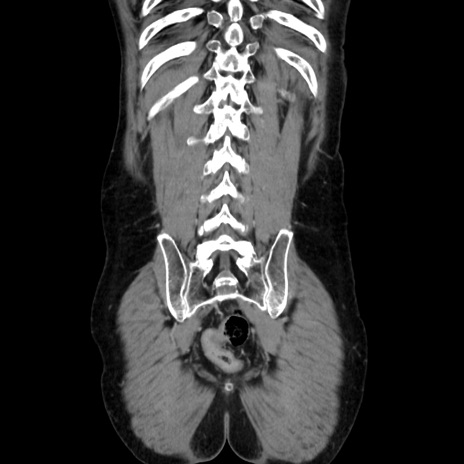

症例37(冠状断像)

【症例】40歳代 男性

【主訴】腹痛

【現病歴】4時間ほど前に電車に乗車中に臍部上より腹痛出現。徐々に増悪し起立困難となり、救急外来受診。生ものは数日食べていない。今朝お雑煮を食べた。

【身体所見】BT 36.8℃、BP 117/84mmHg、HR 91/min、SpO2 97%、苦悶様、腹部:臍上部広範囲圧痛あり、反跳痛±

【データ】WBC 8100、CRP 0.03